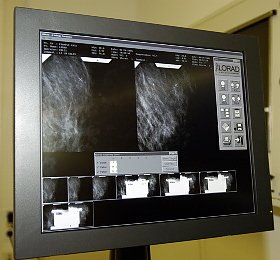

Es trifft jede neunte Frau (Foto: nnz)

Das Stereotaxiesystem Multi Care, welches eine Untersuchung der Frauen im Liegen ermöglicht, macht die Untersuchung ganz einfach. Die Brust wird von einer speziellen Vorrichtung festgehalten und geröntgt. Auf dem Monitor sieht Dr. Ansgar Malich dann genau, wo sich die Kalkablagerungen befinden. Mit Hilfe zweier Bilder aus unterschiedlichen Perspektiven kann er berechnen lassen, wie tief sich der Kalk im Gewebe befindet. Alle drei Koordinaten gibt der Computer an das Steuergerät für die Biopsie weiter. Eine etwa 2 mm dicke Führung wird dann in die Brust gestochen. Liegt sie an der richtigen Stelle, folgt die Vakuumbiopsienadel. Durch einen Unterdruck wird ein Teil des Gewebes eingesaugt und schließlich mit einem eingebauten, runden Skalpell abgetrennt. Wird die Nadel wieder herausgezogen, bleibt nur eine winzige Narbe von zwei bis drei Millimetern. Das entnommene Gewebe wiegt nur ein paar Gramm. Sind die Kalkablagerungen harmlos, dann bleiben keine Beeinträchtigungen zurück. Die Brust sieht genauso aus wie vorher. Ist es doch Krebs, dann muß operiert werden. Die bösartigen Tumore können computergestützt genau markiert werden. So kann der operierende Gynäkologe das betroffene Gewebe leichter wiederfinden und schonender operieren.